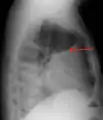

A pleural effusion as seen on lateral upright chest x-ray- Pleural effusion as seen behind the heart.[17]